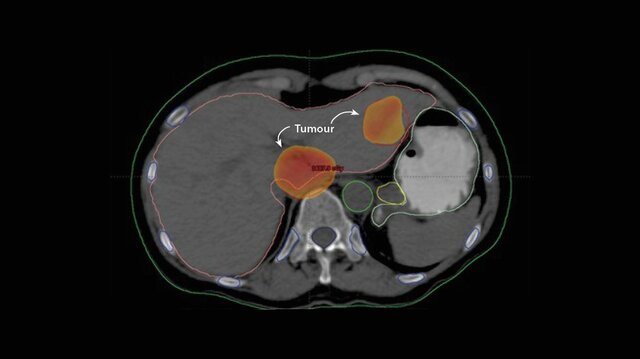

• Tomografía computarizada

Tomografía computarizada

Cambia por completo el mundo de la imagen diagnostica, siendo realizada por primera vez por Hounsfield, preguntándose sobre si podría reconocer el contenido de una caja tomando una gran cantidad de lecturas de toda la caja